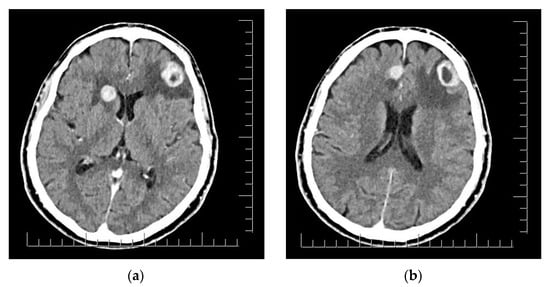

2. Case Presentation